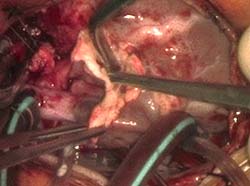

Congenital Supravalvar Aortic Stenosis Repair

We present the operative steps in the repair of congenital supravalvar aortic stenosis in a 5 month old female of 8kg. Preoperative echocardiography and cardiac magnetic resonance imaging confirmed severe biventricular hypertrophy together with pulmonary stenosis and supravalvar aortic stenosis. We detail the steps for the three-patch technique of repair of the left ventricular outflow tract obstruction using pulmonary homograft patches. The results were satisfactory, and the patient was discharged home in timely fashion.